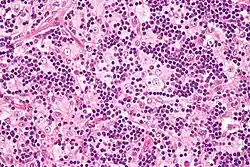

Es zeigt sich eine ausgeprägte, beidseitige Vergrößerung der zervikalen Lymphknoten, die hauptsächlich auf die Verbreiterung der Sinus der Lymphknoten zurückzuführen ist. Diese Sinus sind mit aktivierten Histiozyten gefüllt, die intakte Erythrozyten und Lymphozyten umhüllen, was als Emperipolese bezeichnet wird.[4][5]

Gleichzeitig findet in den Sinus eine Vermehrung von Plasmazellen, Lymphozyten und neutrophilen Granulozyten statt. Auch andere Lokalisationen sind möglich: so können Herde in der Haut, der Hirnhaut, dem oberen Respirationstrakt, Speicheldrüsen und Knochenmark auftreten.[5]